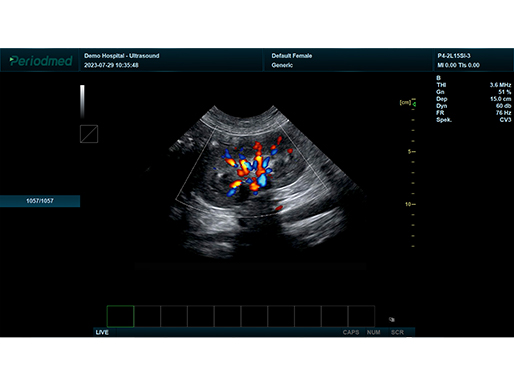

彩色多普勒模式 脾 狗

彩色多普勒模式 肝 猫

微凸探头-彩色多普勒模式-脾 狗

微凸探头-彩色多普勒模式-肾 狗

微凸探头-彩色多普勒模式-肝 猫